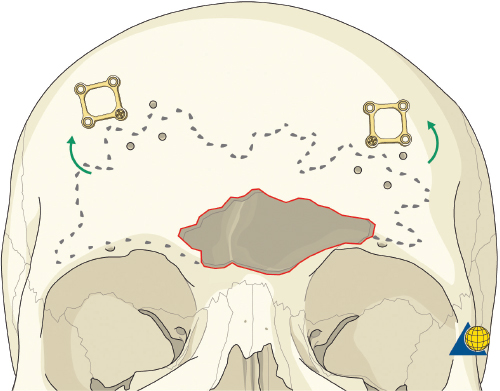

Frontal Sinus Obliteration

More severe injuries involving the anterior and/or posterior table(s) may require sinus obliteration. The exposure has been described above (open reduction and internal fixation). It is important to maintain a viable pericranial flap that can be used for dural repair if necessary. After complete exposure of the frontal bone (and orbital rims as necessary), all anterior table bone fragments should be carefully removed and kept moist on a side table. It is helpful to maintain the orientation of the fragments with a drawing to assist with re-orientation during the final repair ( Fig. 63.35 ). It is often necessary to complete the frontal sinusotomy, and remove any remaining anterior table bone to visualize the entire sinus. Intraoperative navigation can be useful to define the margins of the sinus. Alternatively, one tine of a bipolar cautery can be placed through a defect in the anterior table and walked around the periphery of the sinus. The outer tine is used to mark the outline of the sinus externally ( Fig. 63.36 ). Transillumination can also be used to outline the sinus. A light source is placed within the sinus, illuminating the periphery, which is then marked in a similar fashion ( Fig. 63.37 ). After the limits of the sinus have been marked, several microplates are pre-applied across the proposed osteotomy sites ( Fig. 63.38 ), maintaining the precise location of the bone flap at the completion of the procedure. The plate is rotated superiorly and the osteotomy is performed ( Fig. 63.39 ). The author prefers a high-speed Midas Rex drill (Medtronic, Inc.) and a B-1 bit. The same tool can be used to make perforations along the periphery of the sinus ( Fig. 63.40 ), and complete the osteotomy by joining the perforations with side cutting capabilities ( Fig. 63.41 ). The osteotomy line should be angled toward the sinus cavity to avoid intracranial penetration ( Fig. 63.42 ). The orbit rims and glabella can be osteotomized with either the drill or osteotomes depending on the degree of preexisting comminution; however, the surgeon must protect the supratrochlear and supraorbital neurovascular pedicles. Finally, an osteotome is inserted through the superior saw kerf and used to break down any intersinus septations, and bone flap is removed ( Fig. 63.43 ).